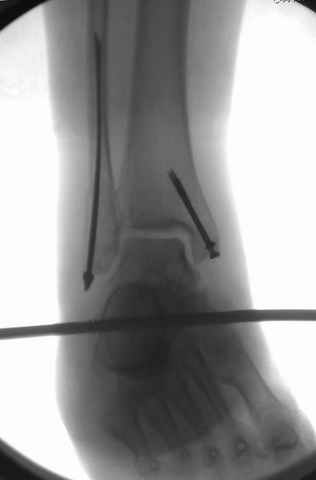

На снимках варианты фиксации малоберцовой:

№ 6-11 при pilon percutaneus fixation

DK> № 6-11 при pilon percutaneus fixation

А если без? Результат был бы хуже?